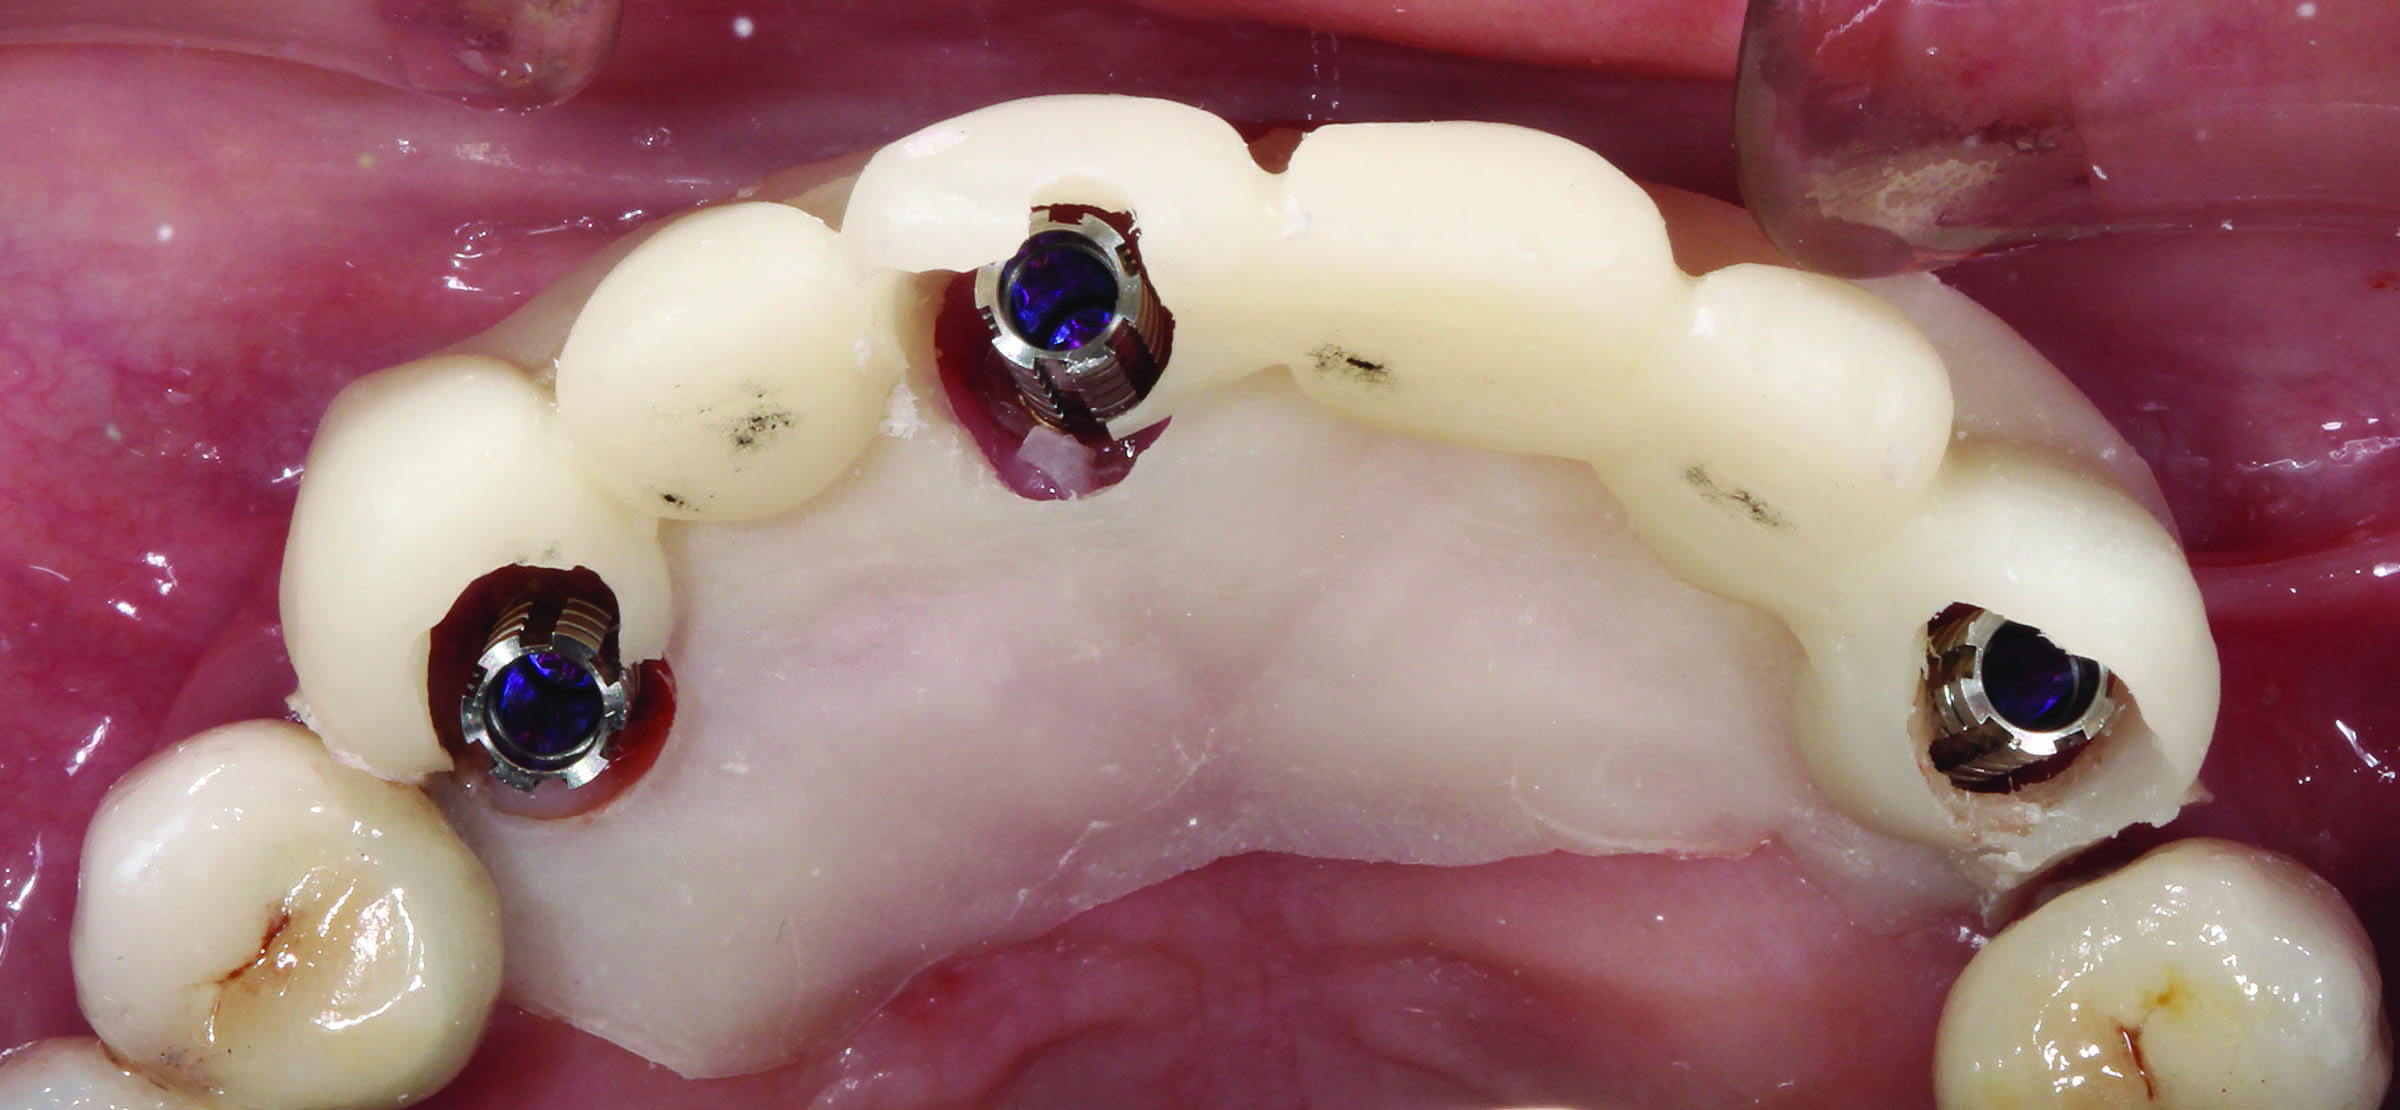

Fig 9. This screw-retained implant-supported provisional prosthesis is laboratory-processed.

Figure 9